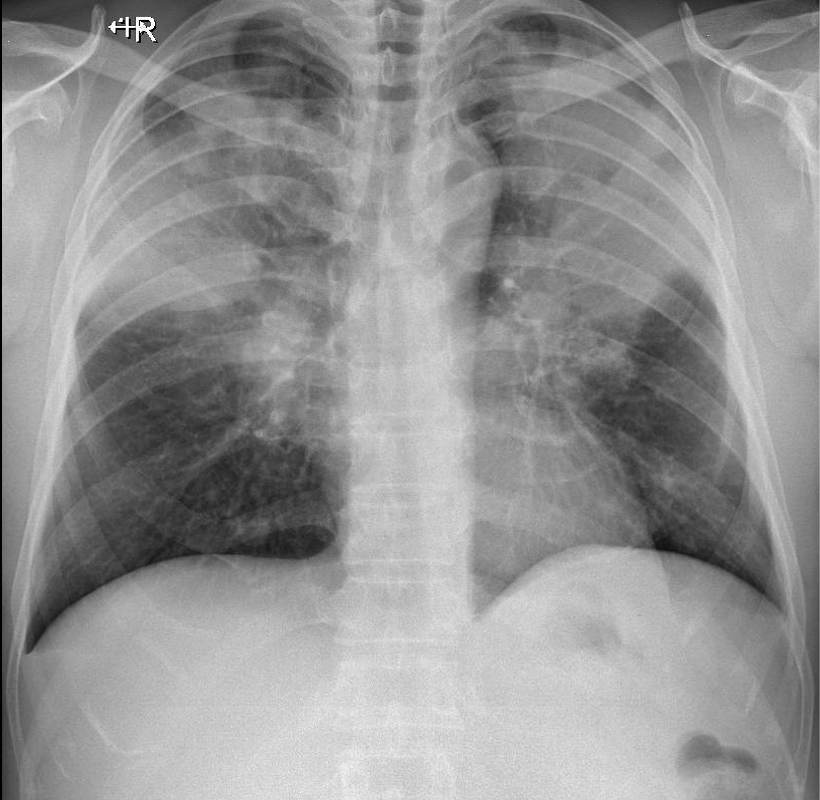

Hãy phân tích tình huống nam 52 tuổi

1-Tổn thương phế nang mờ đồng nhất lan tỏa thùy trên hai phổi => Viêm phổi